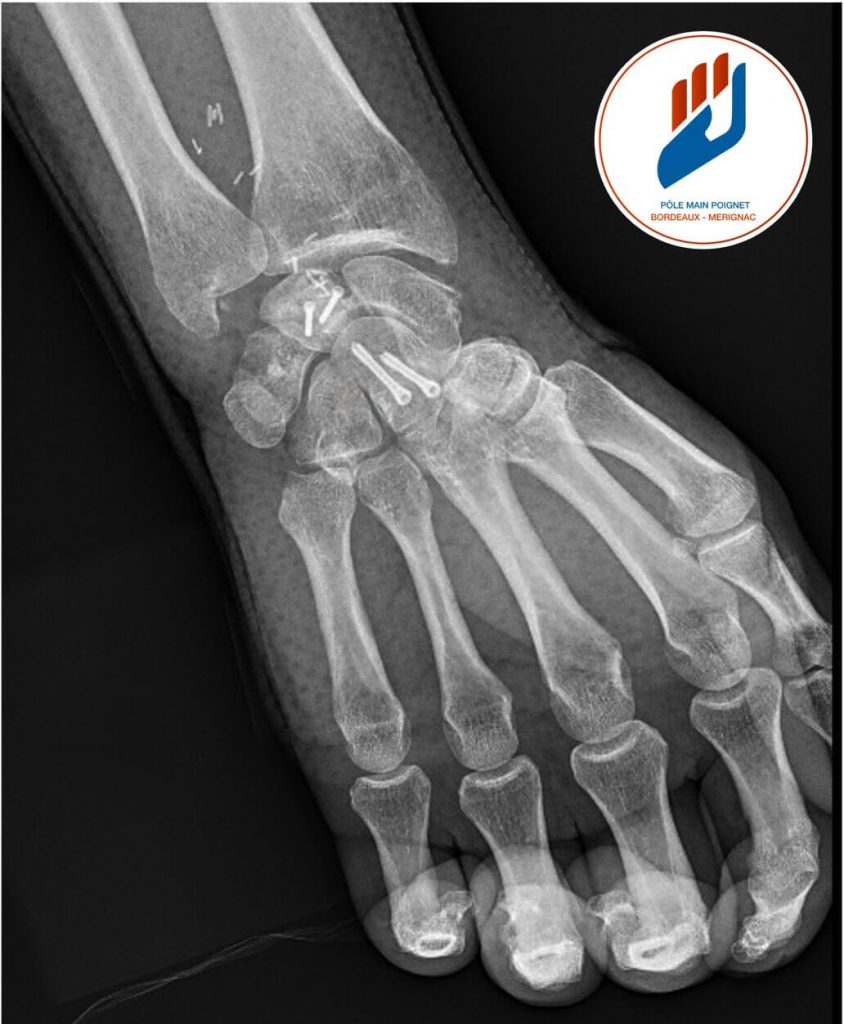

L’imagerie joue un rôle essentiel dans le diagnostic de la maladie de Kienböck et permet de déterminer son stade. La radiographie standard reste le premier bilan à réaliser. Elle permet de voir les fractures ou la déformation du lunatum dans les formes avancées de la pathologie. Cependant, les premiers stades de la nécrose peuvent ne pas être visibles sur les radiographies classiques.

Traitement chirurgical : Arthrodèse du carpe ou résection de la première rangée dans la maladie de Kienböck

- L’arthrodèse partielle du carpe

Elle consiste à fusionner certains os du carpe (arthrodèse scapho-capitate, voire scapho-trapézo-trapézoïdienne associée). Cette intervention stabilise le poignet, diminue les mouvements anormaux responsables de douleurs et permet une amélioration fonctionnelle. La mobilité est réduite, mais la force et la stabilité sont améliorées. - La résection de la première rangée du carpe (PRC)

Cette technique consiste à retirer le scaphoïde, le lunatum et le triquétrum. Elle conserve un certain arc de mobilité du poignet tout en supprimant la douleur liée aux surfaces articulaires détruites. Son efficacité dépend toutefois de l’intégrité du cartilage de la tête du capitatum et de la surface radiale : si ceux-ci sont trop altérés, les résultats sont moins satisfaisants.